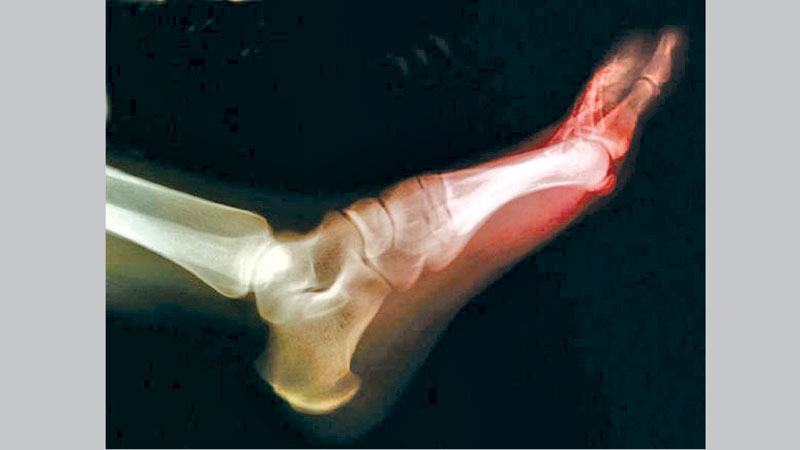

Warding off the joint pain of gout may be as easy as eating right, a new study suggests. Gout, a joint disease that causes extreme pain and swelling, is caused by excess uric acid in the blood. It's the most common form of inflammatory arthritis, and its incidence has risen among Americans over recent decades, Harvard researchers noted.